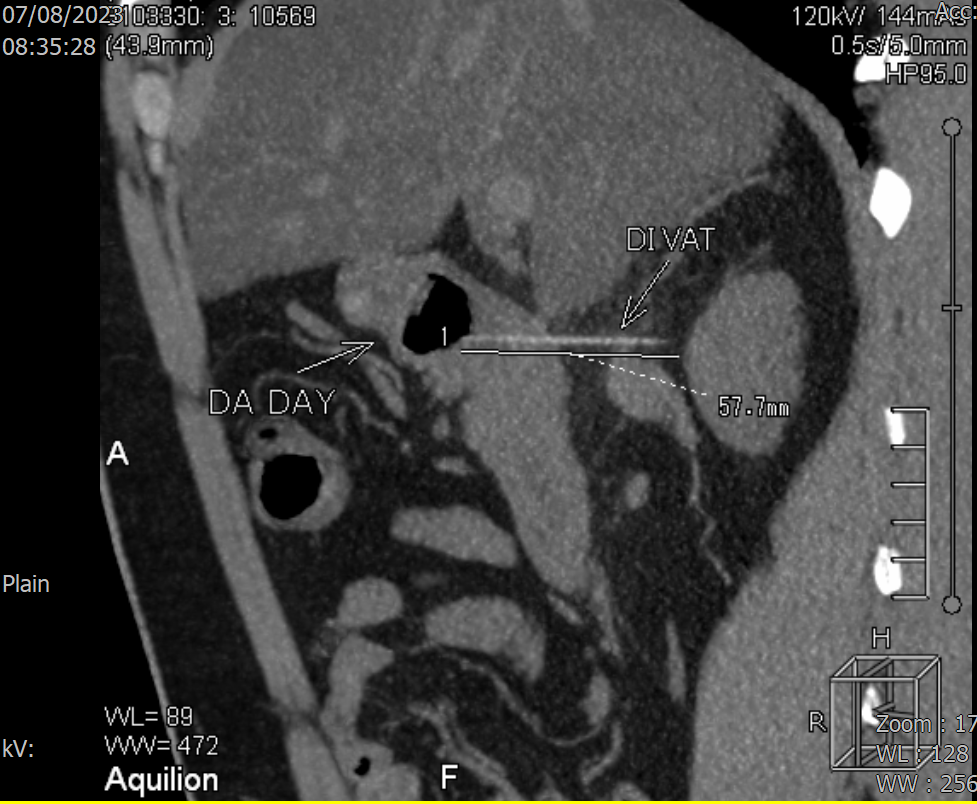

Tại Khoa Cấp cứu, nhận định ông Q. có khả năng bị thủng dạ dày do nuốt phải dị vật, các bác sĩ chỉ định ông Q. thực hiện chụp CT bụng chậu khẩn. Kết quả phát hiện dị vật dạng que thẳng, đường kính 2mm dài 4,5cm xuyên thành mặt sau hành tá tràng vào mô mỡ phúc mạc.

Hình ảnh CT bụng chậu phát hiện dị vật